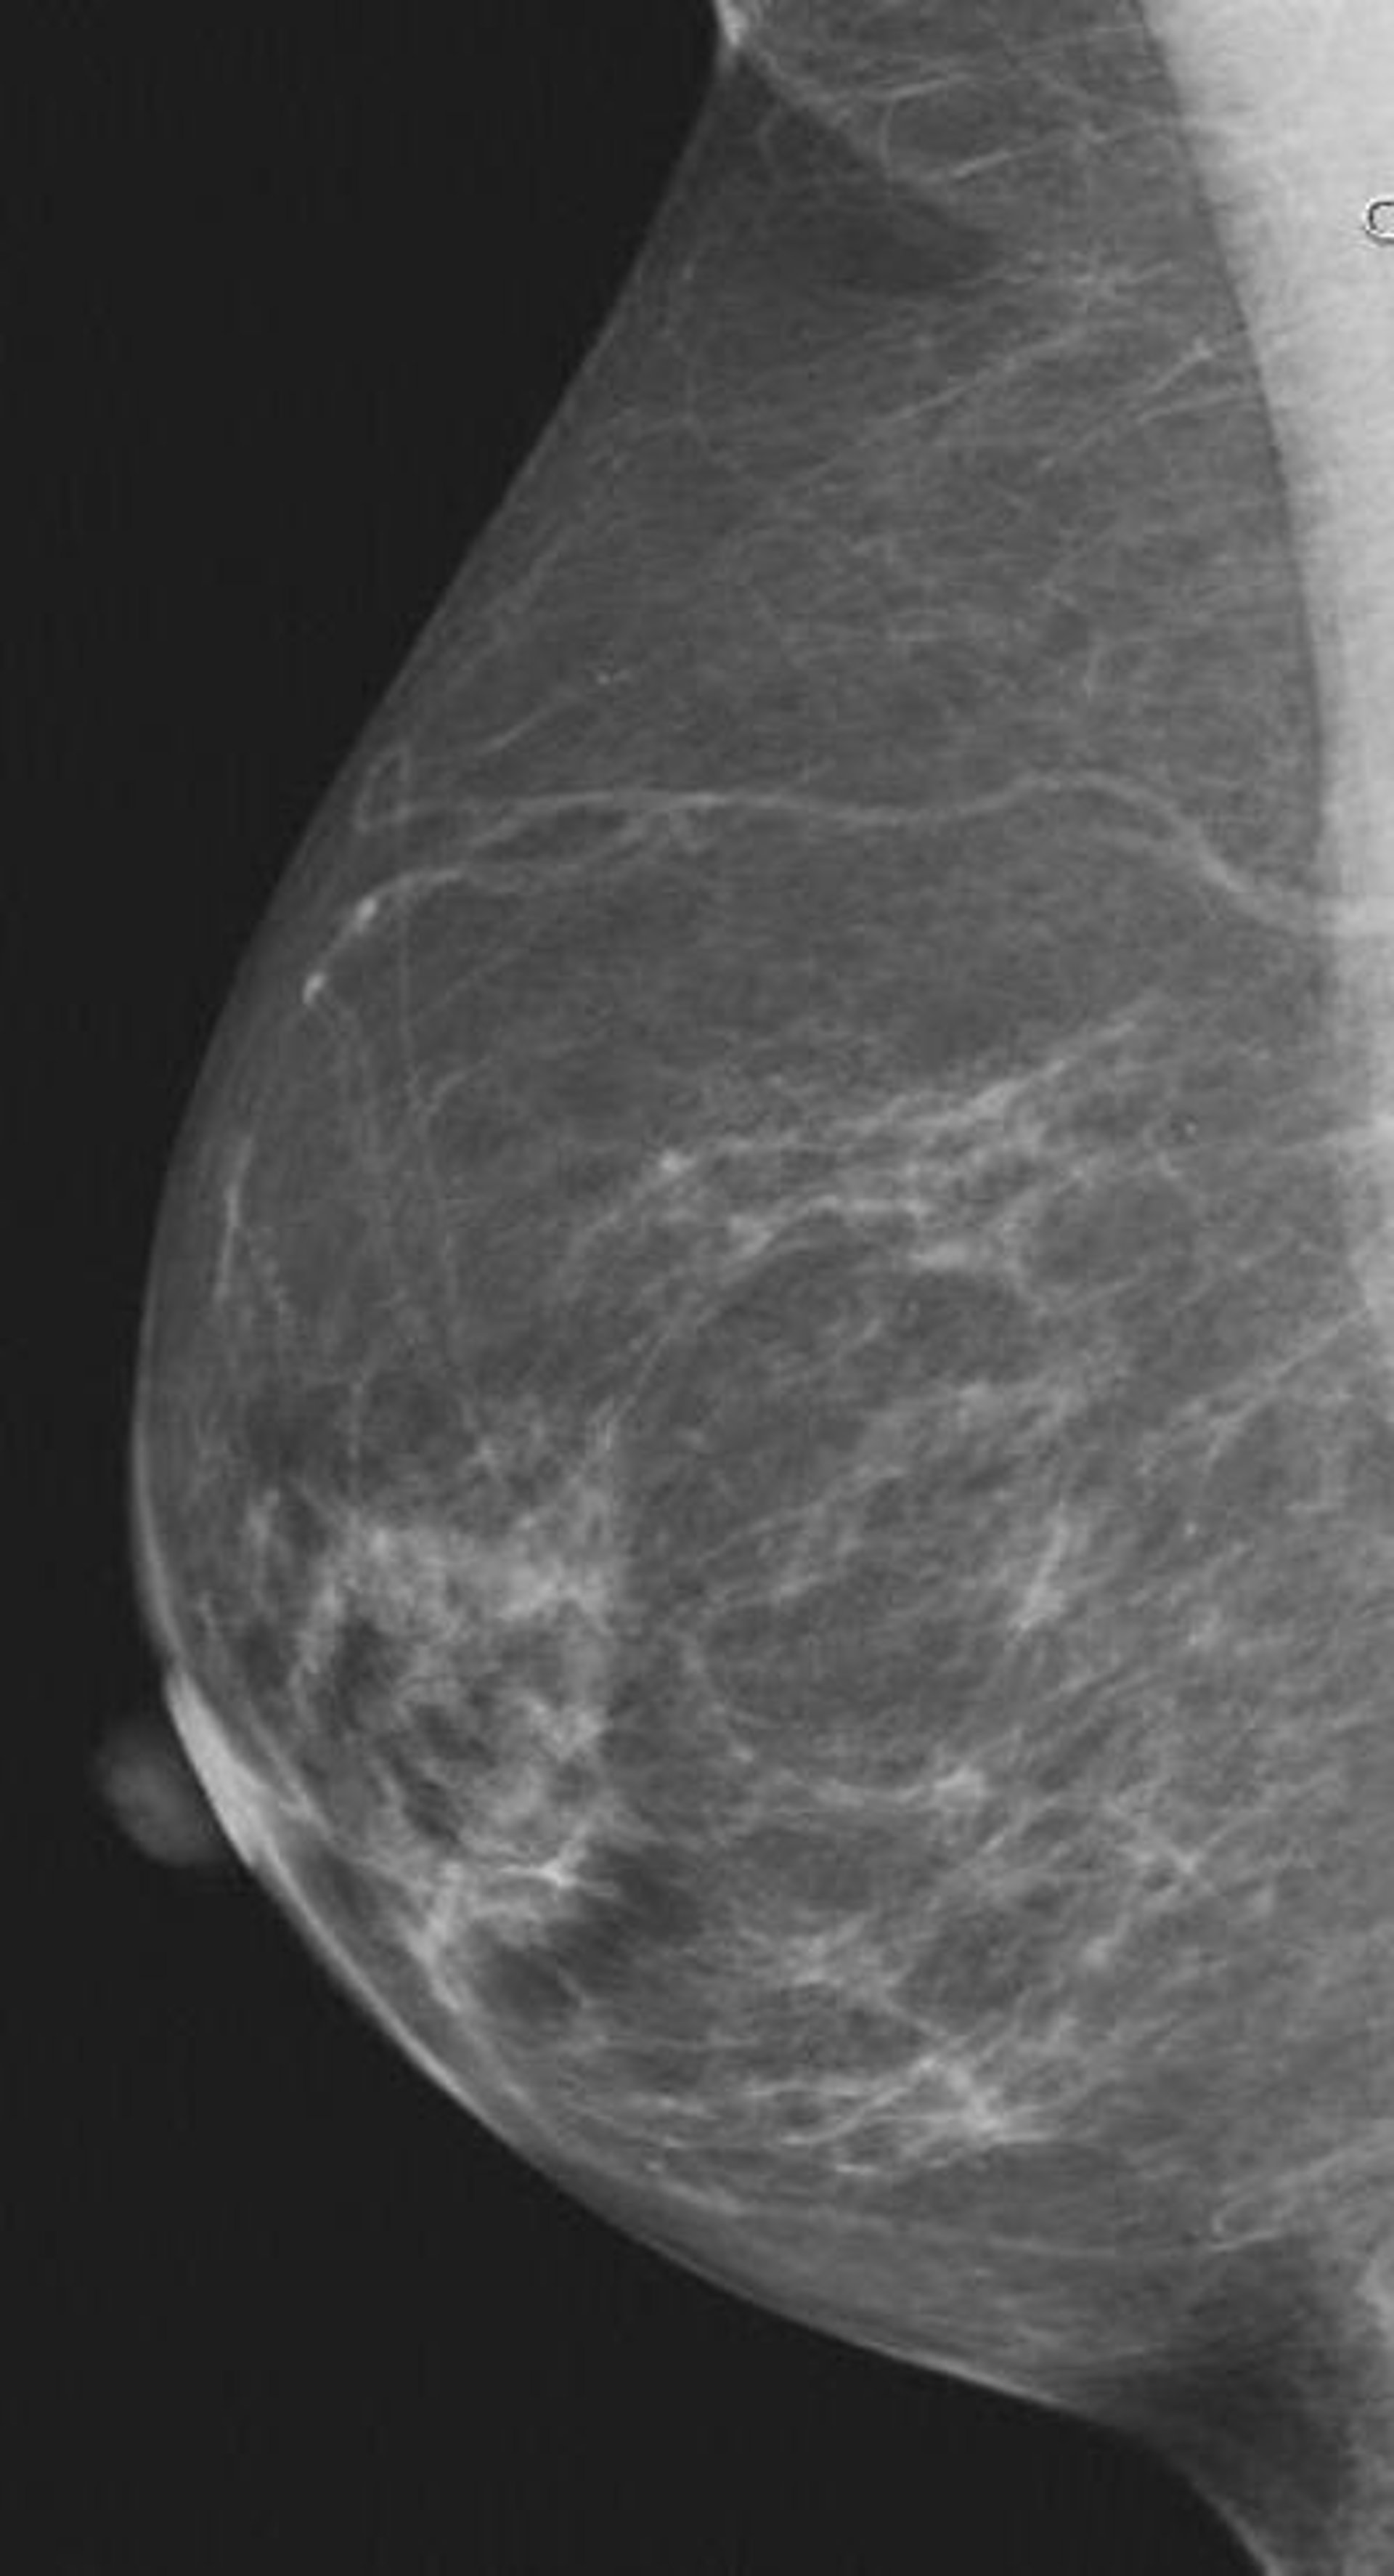

Las ecografías pueden ayudar a diagnosticar el cáncer de mama en mujeres con senos densos, según ha mostrado una investigación liderada por el doctor del Hospital Magee-Womens de la Universidad de Pittsburgh Medical Center (Estados Unidos), Wendie Berg.

Durante más de tres años, se sometió a las participantes a mamografías y ecografías, detectando en total 111 casos de cáncer de mama, el 80 por ciento de los cuales eran invasivos. En este sentido, los científicos compraron que las mamografías y las ecografías descubrieron aproximadamente el mismo número de tipos de cáncer.

Ahora bien, las primeras detectaron mejor el carcinoma ductal in situ (CDIS), el tipo más común de cáncer de mama no invasivo, mientras que con las ecografías se detectaron mejor los cánceres invasivos aunque, tal y como han reconocido los expertos, mostraron más falsos positivos.